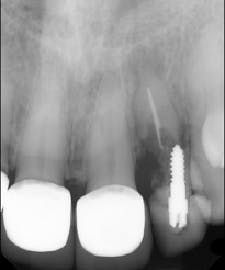

Tooth No. 10 was extracted. The socket was disinfected with chloramine-T gauze. An immediate implant (4.3 mm x 10 mm with a 5 mm healing screw) was placed (figure 2).

The patient presented to restore the implant six months later with a predicted large vertical and horizontal tissue defect (figure 3). The implant was restored with gingival ceramics to compensate for the ridge defect (figure 4).